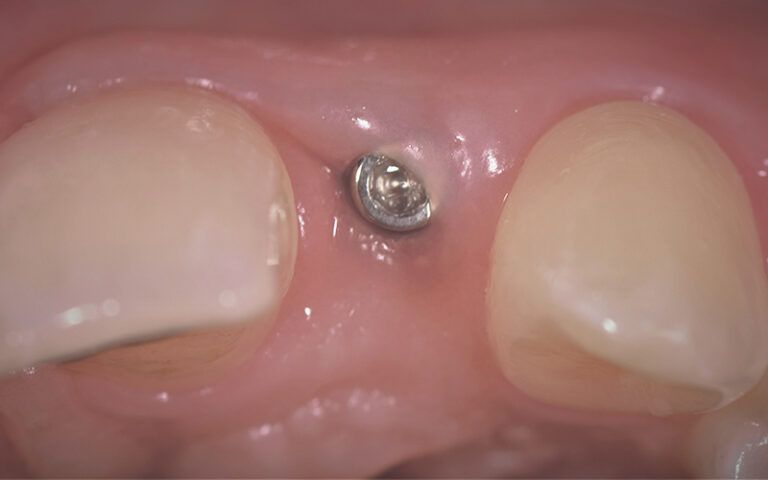

Images of the osseointegration period of the implants and healing of the tissues Images of the osseointegration period of the implants and healing of the tissues Images of the osseointegration period of the implants and healing of the tissues Images of the osseointegration period of the implants and healing of the tissues

After three months of osseointegration, the second surgery performed on both implants and the digital impressions were taken with the TRIOS (3Shape) intraoral scanner.